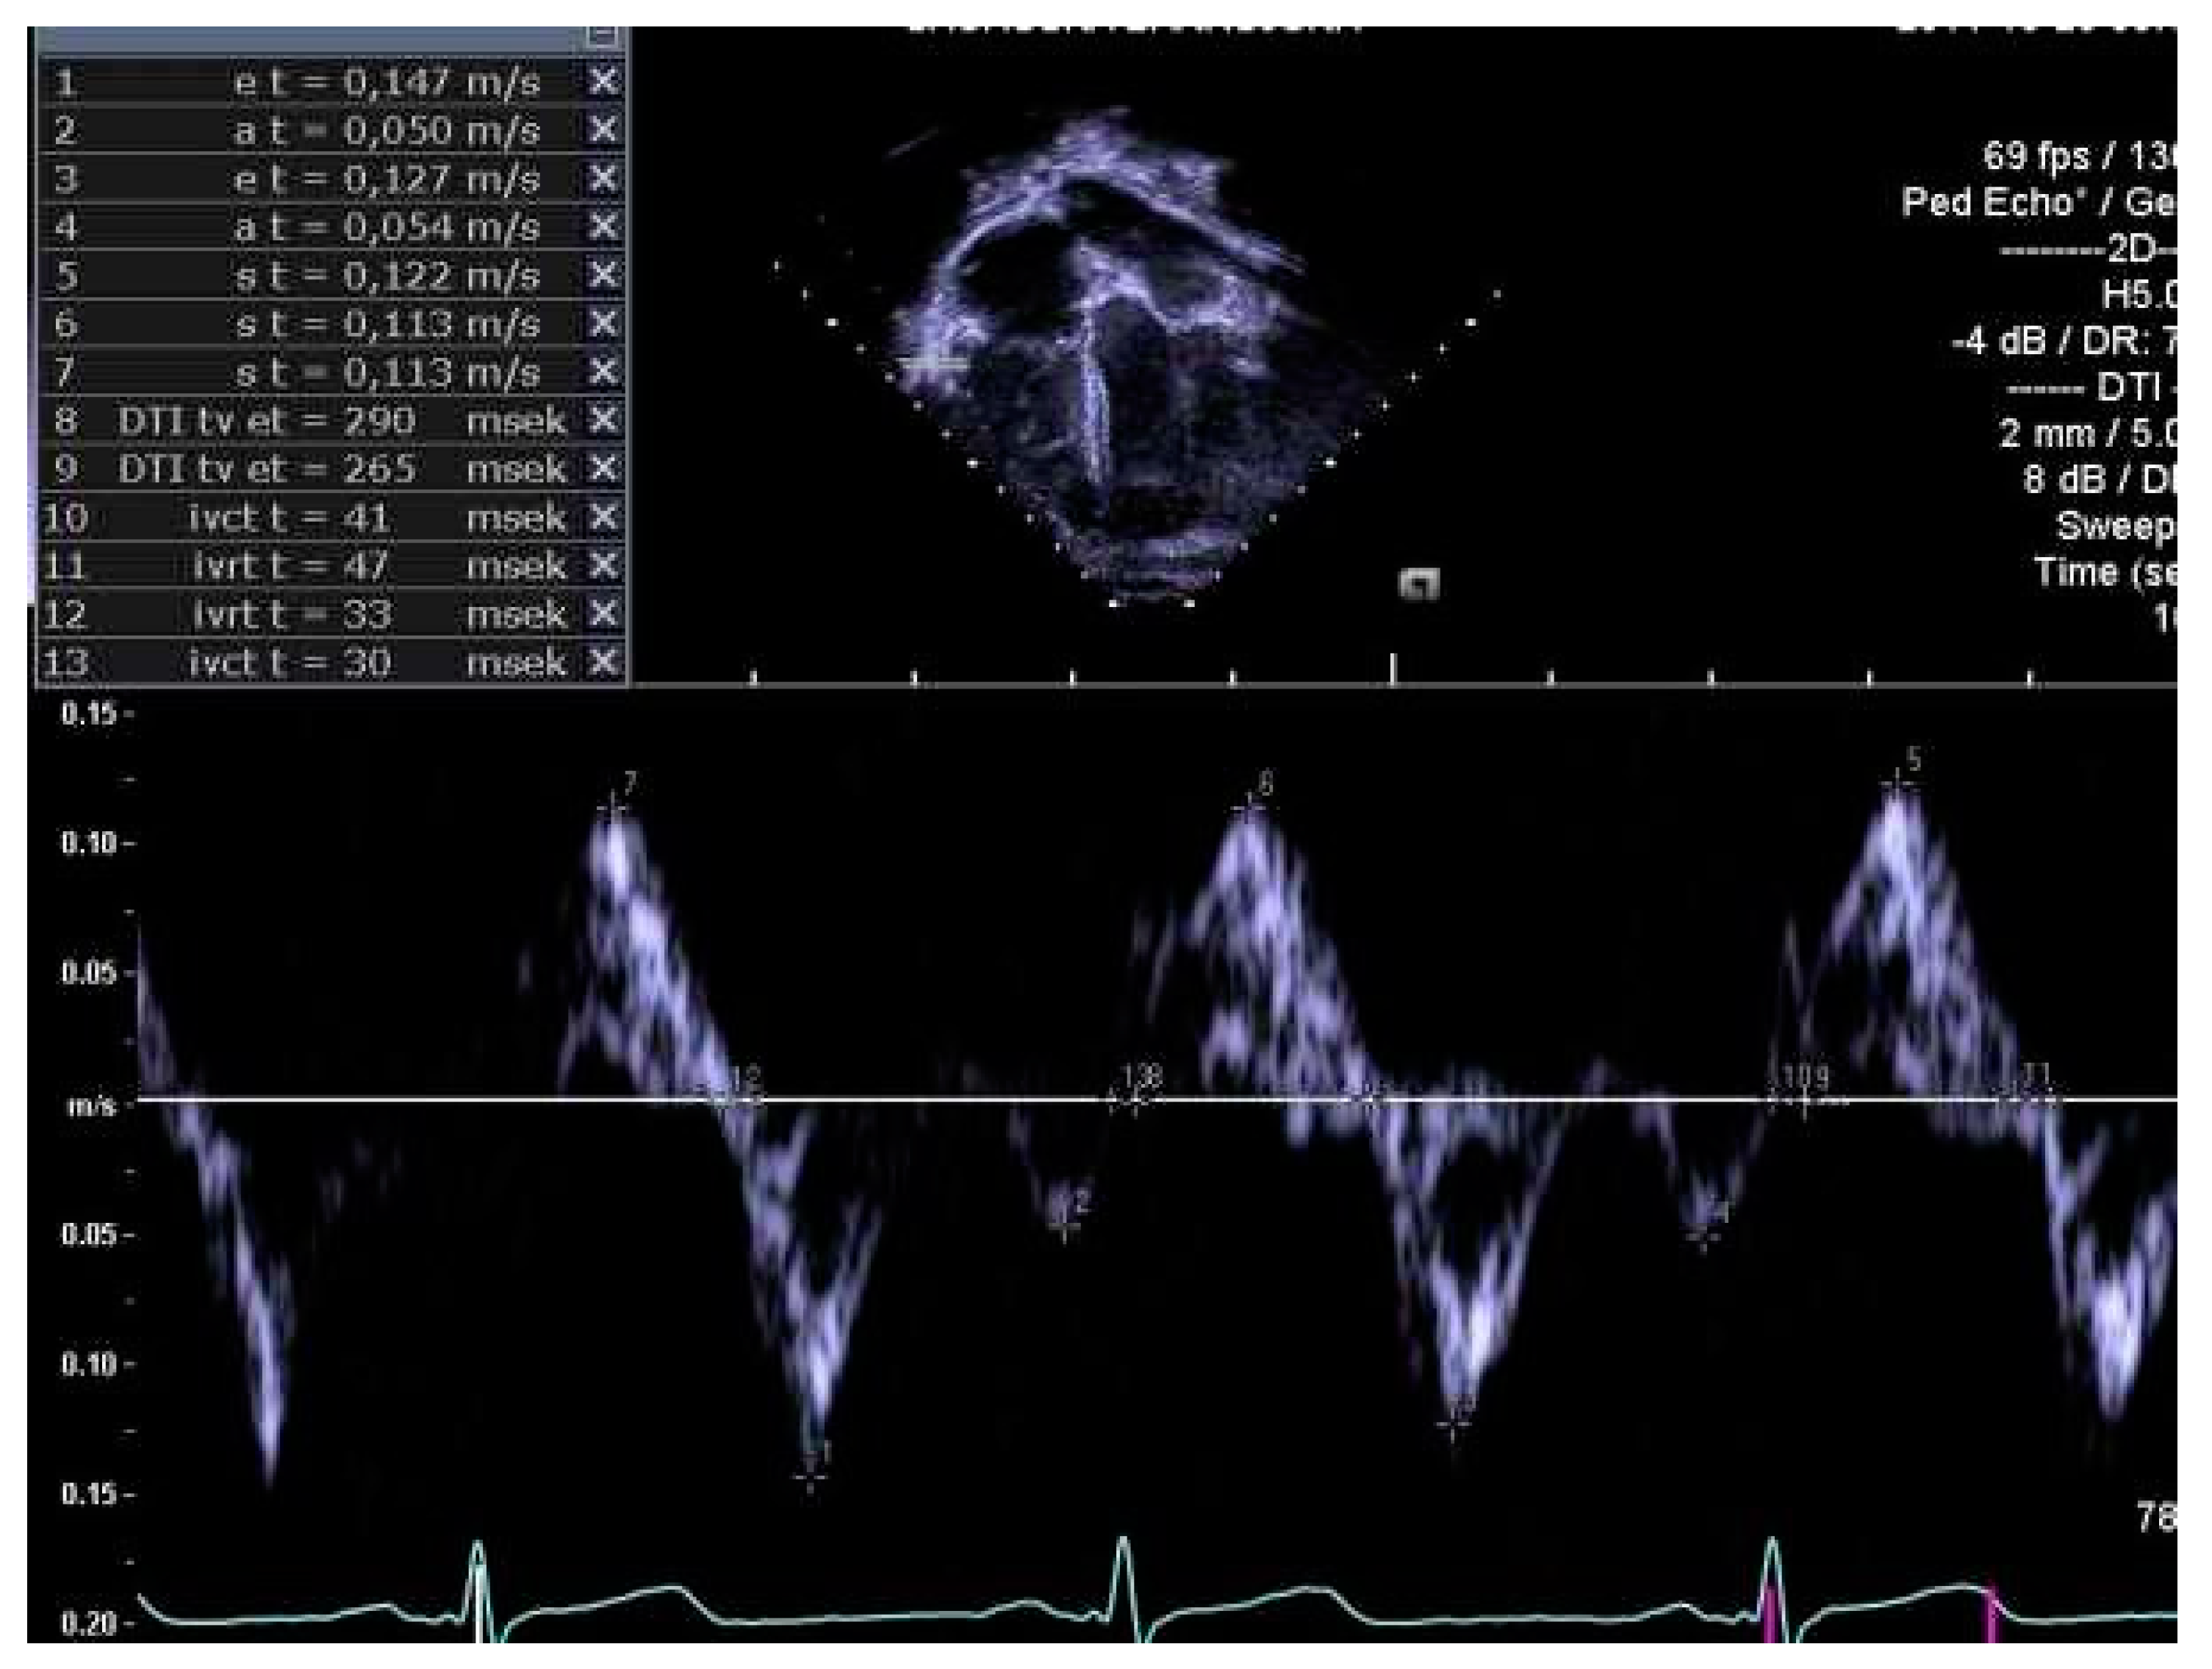

Figure 4.

Right ventricular myocardial performance index (RVmpi’) assessed by pulsed wave tissue Doppler of right ventricular free wall.

The same experienced cardiac sonographer at each centre investigated all participants and followed a predefined standardized protocol. Image analyses of the right heart and the pulmonary arteries, as well as systolic and diastolic functions acquired with 2D echocardiography and blood- and tissue Doppler, were performed off-line by two operators: one (LAM) for recordings from Stockholm and Umeå, and another (OB) for Lund. Both operators were blinded to group belonging, and vascular dimensions as well as systolic and diastolic functions were determined using similar techniques as in previously reports of the systemic arteries and left heart [9,10]. RV volumes were calculated with velocity time integral for right ventricular outflow tract (RVOTvti) estimated by pulsed wave Doppler (PW) and pulmonary valve annulus diameter (PVann), Figure 1. RV relative wall thickness (RWT) was calculated as (anterior wall + interventricular septum)/ RV width. Sphericity index (SI) was calculated as diameters for length/width for the atrium and ventricle, respectively. Pulmonary vascular resistance (PVR) was estimated by Doppler, calculating the ratio using the simplified formula described by Abbas et al. 2003, for tricuspid valve regurgitation (TR), Figure 2, divided by RVOTvti [20]. Systolic function was evaluated by tricuspid annular plane systolic excursion (TAPSE), Figure 3 and diastolic function was assessed by early (E) and late (A) velocities of the tricuspid valve with pulsed wave and, with tissue Doppler (s’, e’, a’). To estimate RV filling pressure, the E/e’ ratio was calculated. Systolic ejection time (et), isovolumic relaxation time (ivrt) and isovolumic contraction time (ivct) were assessed with tissue Doppler to calculate right ventricular myocardial performance index (RVmpi’), using the formula (ivrt + ivct)/et, Figure 4.

Systolic function expressed as TAPSE was lower in EXPT compared with CTRL after adjustment. RV myocardial systolic velocity (s’) of the free wall and interventricular septum showed no differences between EXPT and CTRL. Adjusted RVmpi’ of the free wall assessed with tissue Doppler was slightly lower in EXPT than in CTRL.

Except for shorter myocardial isovolumic contraction times (ivct) of the septum and the free wall in EXPT than in CTRL, there were no statistically significant differences in diastolic function between the two groups, Table 3. Intraobserver variability expressed as coefficient of variation for echocardiographic assessments of pulsed Doppler RVOTvti was 5.2%.